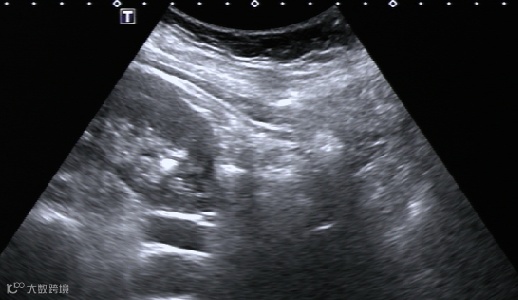

肝脓肿抽液治疗:

治疗前

治疗后